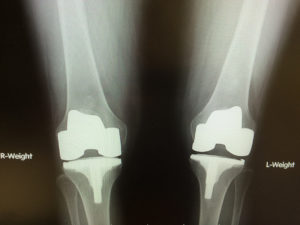

Full vs. Partial Knee Replacement

There are many reasons people have knee replacement surgery, including rheumatoid arthritis, osteoarthritis, traumatic arthritis, or an injury. These issues can cause knee pain while walking, standing, or just trying to get up from a chair after being seated for a while. Every year, about 700,000 [Read More]